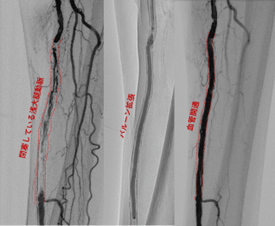

下肢血管の動脈硬化により、歩くと足が痛くなる長距離が歩けなくなる間欠性跛行という症状や、さらに進行し、足に潰瘍や壊死所見が認められる場合は、治療が必要となります。早期の場合は運動療法や薬物療法から開始しますが、それでも症状の改善がない場合や重度の場合はカテーテル治療(EVT)と呼ばれるバルーンやステントによる治療が必要となります。カテーテル治療(EVT)は低侵襲であり、短期間の入院で治療を行うことが可能です。カテーテル治療(EVT)が難しい時にはバイパス手術が必要となることもあります。

足の血管の動脈硬化 カテーテル治療